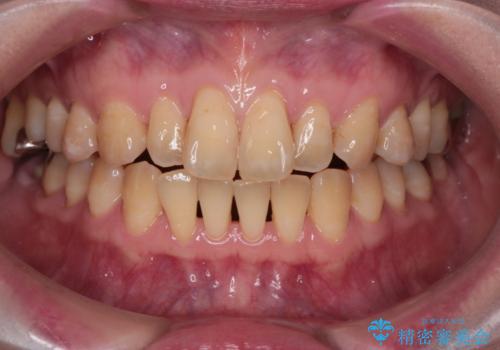

【インビザライン】前歯の捻れとオープンバイト

- 上の前歯の捻れと、前歯で物が噛めないことを主訴に来院されました。

前歯の翼状捻転とオープンバイト傾向だったため、インビザラインにて矯正を行いました。右下の奥歯は保存不可だったため、抜歯を行いインプラントにて修復を行なっています。

翼状捻転はインビザラインでは苦手とする動きですが、ここまで綺麗に治すことができました。